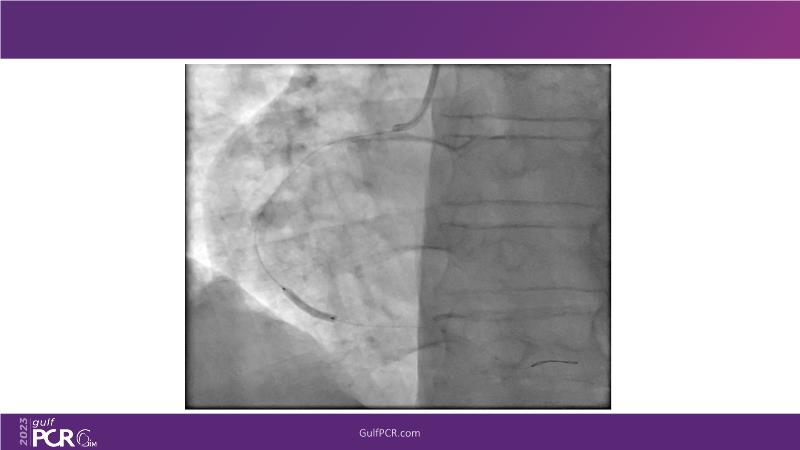

This session is a valuable resource for grasping innovative strategies in handling bifurcation and extended diffuse lesions through dedicated stenting solutions. Explore insights into the advanced Myval next-generation THV technology, unveiling its distinctive features, procedural advantages, and clinical outcomes across a diverse patient pool. Gain understanding into the CorAlign technique, ensuring accurate commissural and coronary alignment while maintaining coronary access. Additionally, delve into the techniques for precise sizing, positioning, and deploying of Myval THV.

- To understand the technique of precise sizing, positioning and deployment of Myval THV